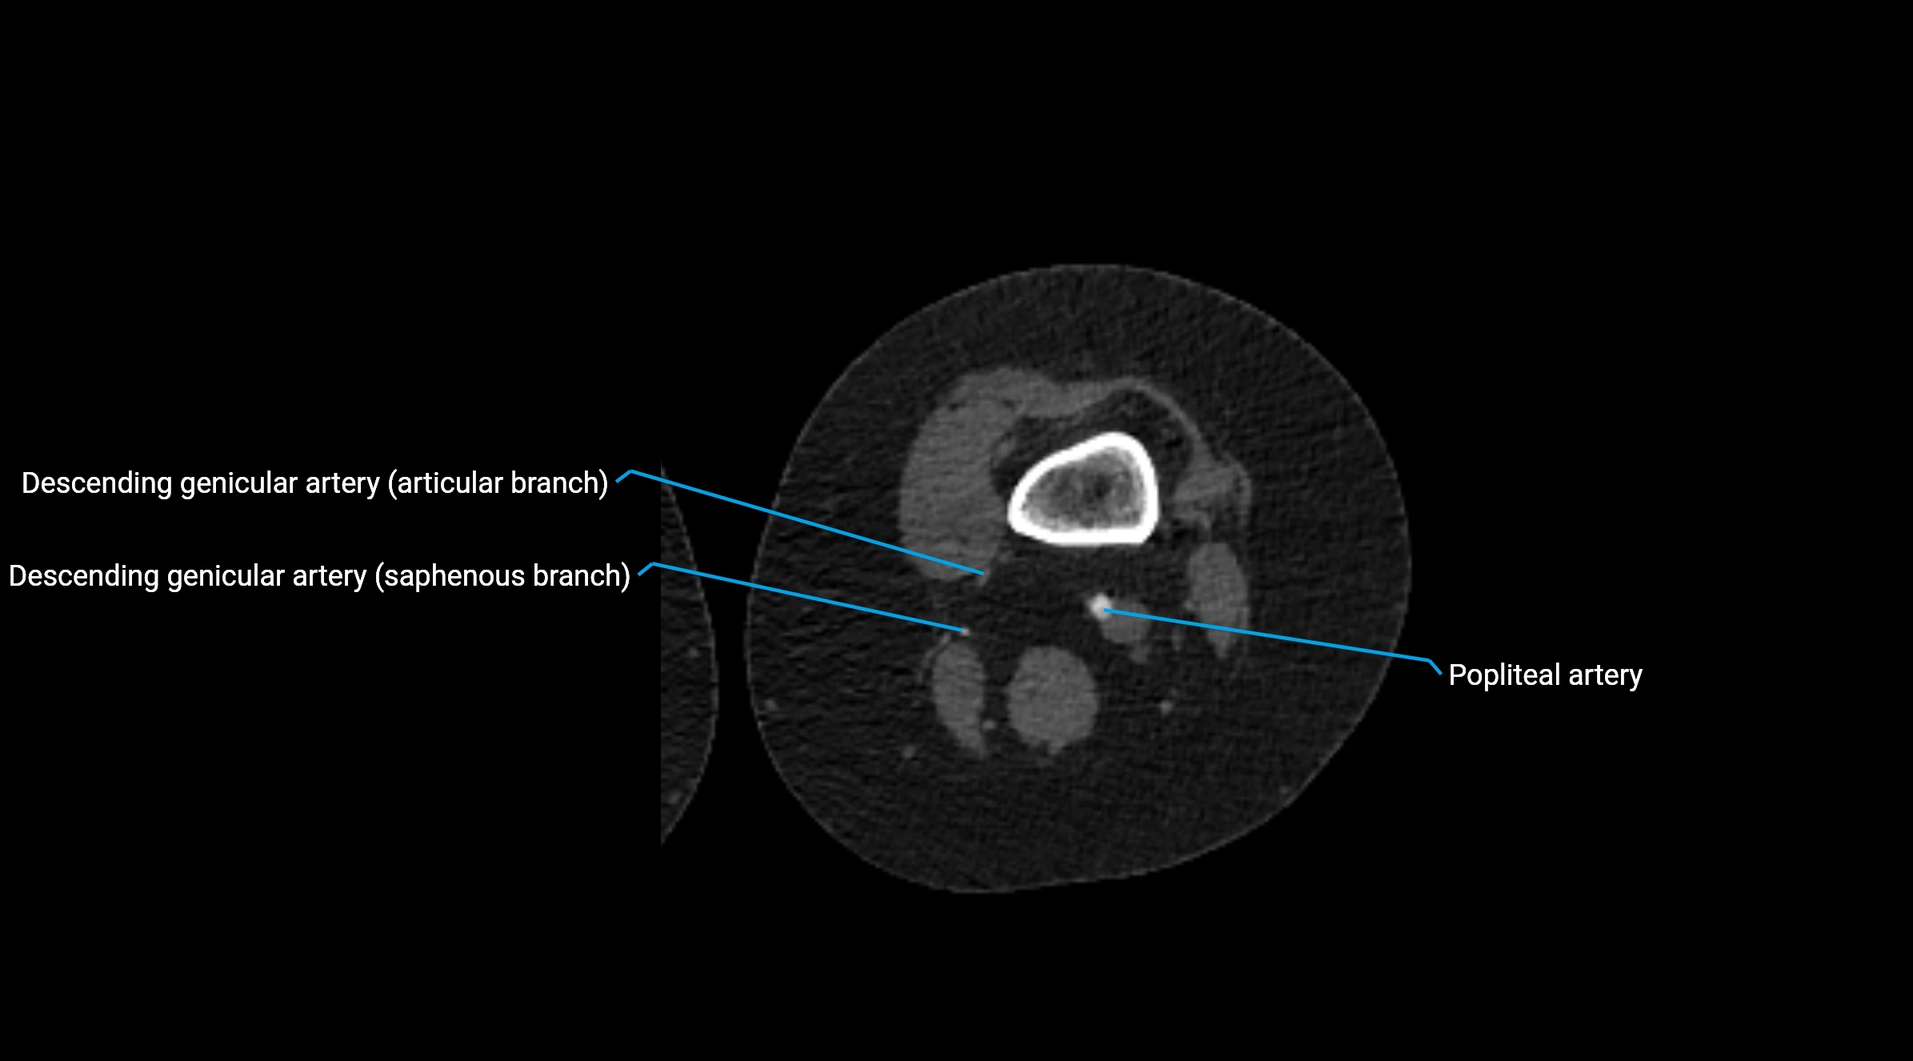

CT Appearance

Non-contrast CT:

• Appears as a tubular soft tissue structure anterior to vertebral bodies

• Calcified atherosclerotic plaques appear as hyperdense foci along the wall

• Useful for screening abdominal aortic aneurysm (AAA) size and mural calcification

Contrast-enhanced CT (CTA):

• Gold standard for abdominal aortic imaging

• Provides excellent detail of lumen, wall, aneurysm, thrombus, and branch vessels

• Multiplanar and 3D reconstructions help in aneurysm measurement, stent graft planning, and dissection evaluation

• Detects acute rupture, traumatic injury, or occlusion with high sensitivity